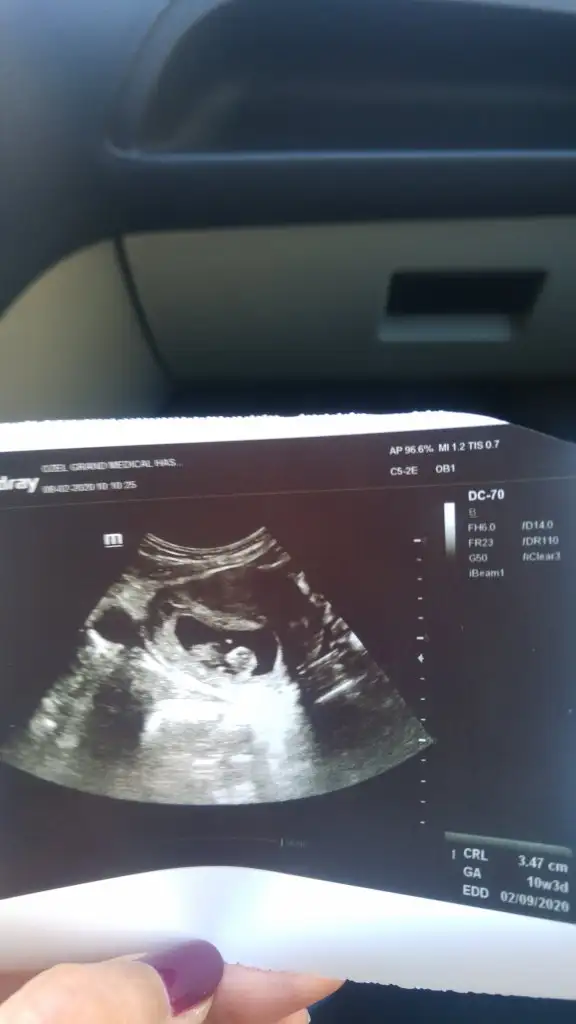

Buda benmm minkmm 3 günn öndenn gidiyorzz 😍😍

Eklentiler

• 20200208_101515.webp

20200208_101515.webp

16,1 KB · Görüntüleme: 98

İkiz değil di mi, sanki soldaki de bir kese gibi😁

Soldaki kese değil. Korpus luteum.Catlayan yumurtası.Bebek gelişimini tamamlayana kadar progesteron salgılayıp gelişimine destek olacak.sonra yavaş yavaş kaybolacak.Hepimizde var.Bende ilk kesemi demistim doktora böyle anlatti